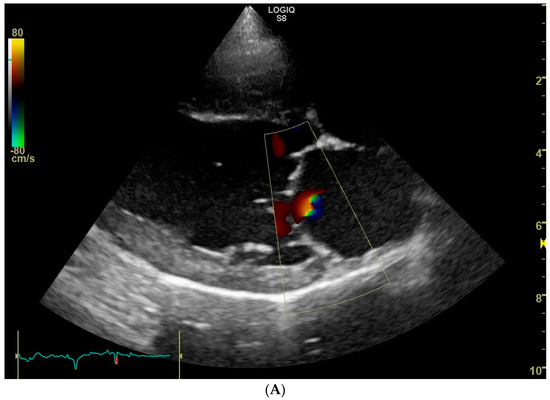

Trivial mitral valve regurgitation was detected in 26 dogs, resulting in a prevalence of 52%. No obvious morphologic changes were noticed on the mitral valve apparatus with 2D echocardiography. Mitral regurgitation appeared central in 24 dogs and eccentric in the remaining 2 dogs, of which in one case two small jets were noticed (Figure 1). Because of the small jet size, no attempts were made to measure the flow velocity of the regurgitant jet with spectral Doppler mode. Mitral valve regurgitation was equally prevalent in female dogs (19/36, 53%) compared to male dogs (7/14, 50%) (p = 0.86). Moreover, mitral valve regurgitation was equally prevalent in black and blonde dogs: 9/16 (56%) in the black and 17/34 (50%) in the blonde ones (p = 0.68).

Figure 1.

Color Doppler echocardiographic images (systolic frames) of trivial mitral valve regurgitation jets in three clinically healthy Labrador retrievers without heart murmur. (A). Standard right parasternal four-chamber view showing a central jet. (B). Standard left parasternal four-chamber view showing a central jet. (C). Standard right parasternal four-chamber view showing two eccentric jets.

Whether the trace mitral valve regurgitation is a physiologic finding, or a manifestation of a mild mitral valve dysplasia in the present study, remains unclear. However, because none of the dogs that underwent an echocardiogram from this dog breeding organization had more than trivial mitral valve regurgitation, mitral valve dysplasia as a possible cause of trace mitral valve regurgitation seems unlikely. As opposed to an assumed physiologic regurgitation, mitral valve dysplasia would likely manifest in various grades of mitral regurgitation. On the other hand, though presumed physiologic mitral valve regurgitations are thought to cause a central jet [5,18], we did identify dogs with an eccentric and more than one jet (Figure 1C).